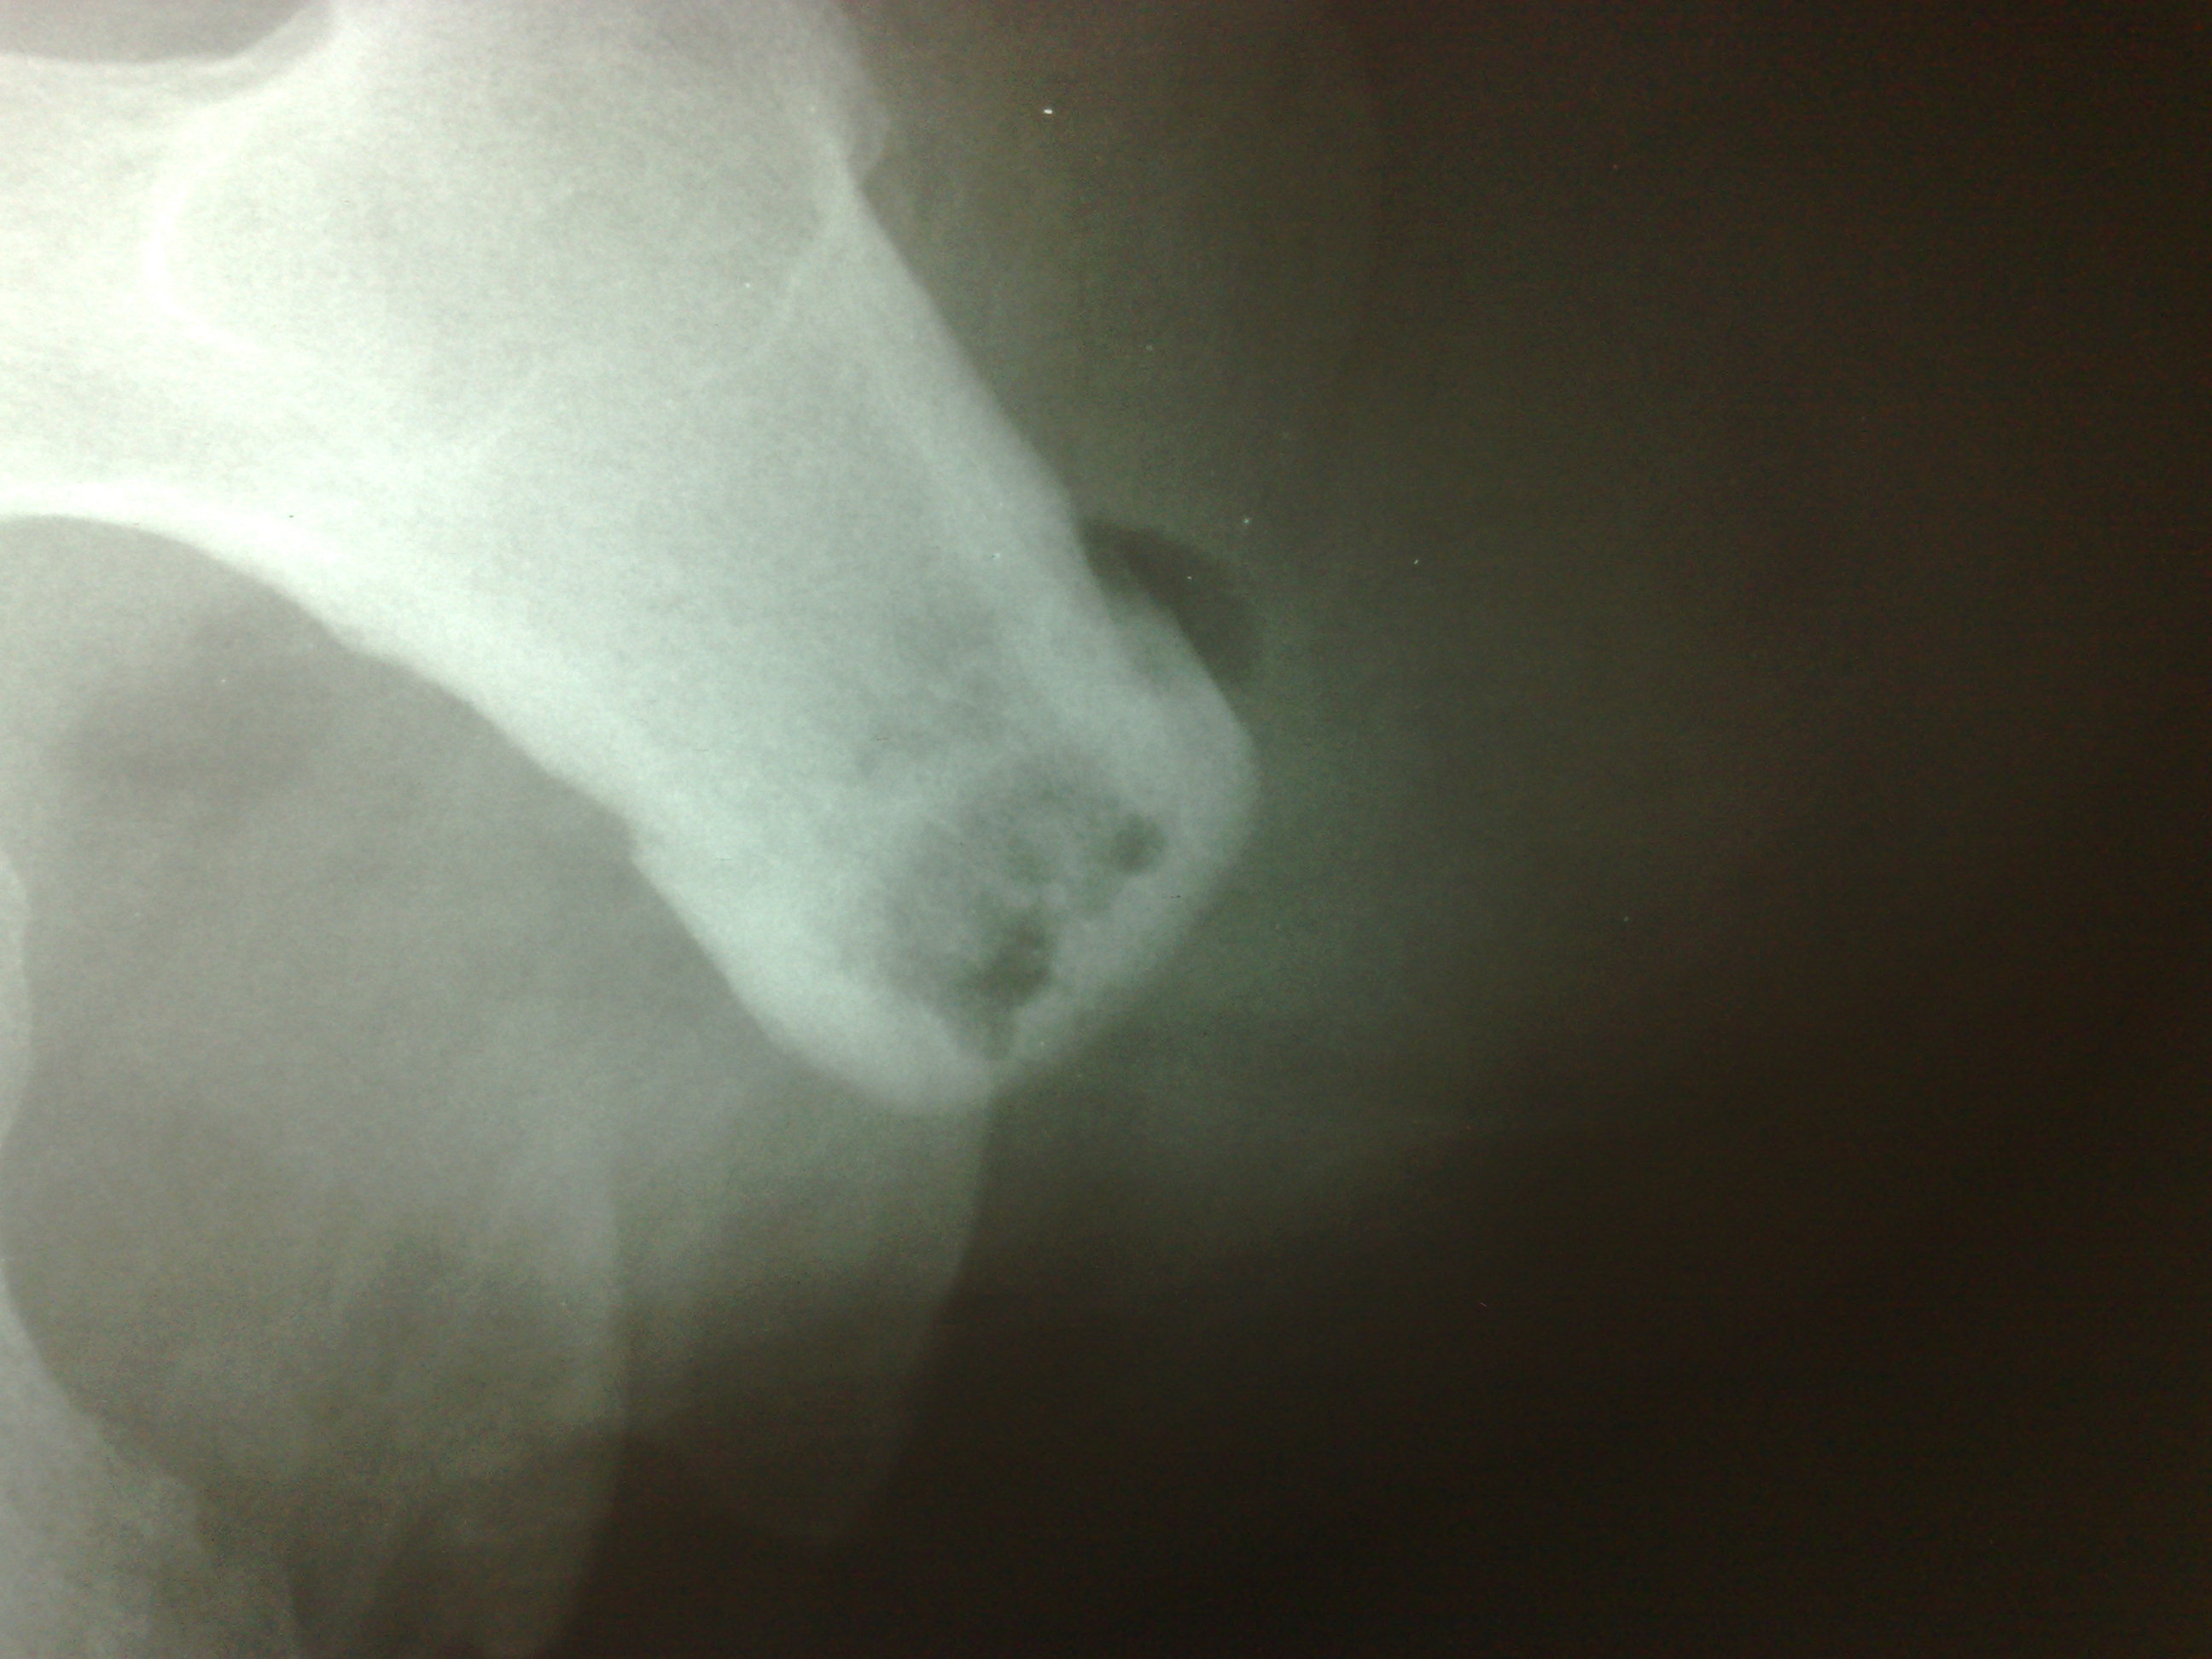

Мужчина средних лет, упал, диагноз: Перфорация культи. В заключении ничего такого страшного я не написала. Приходит хирург и говорит, что у него хр. остеомиелит, как я могла его пропустить. Укажите, пожалуйста, где здесь признаки остеомиелита. Снимки прилагаю:

Наличие газа в мягких тканях видно, признаков хронического миелита (наличие секвестров, костная деструкция, гиперостоз,выраженный периостит) - не вижу. Разве что остеопороз дистального отдела культи... Но не факт, что такая картина обусловлена наличием газа в мягких тканях.

На остеомиелит не похоже. А вот циркулярный (венечный) секвестр может быть. Но это надо выяснять, явно не хватает бокового снимка (лаборантам НЕреспект, все-таки в 2-х проекциях снимать надо).

в доказательство остеомиелита он предлагал внимательнее посмотреть на внутренний контур костно-могзовой полости - что там имеются полости деструкции, а на то, что указано стрелками (утолщение что ли...), ну и еще предлагали посмотреть но костный отпил (он иссек эти полости)

Согласен с переломом. Возможно, с выраженным угловым смещением в перпендикулярной снимку плоскости. Концы отломков образовали якобы "полость просвеления" в дистальном отделе культи.

Он стоит особняком. И имеет не сколько инфекционную/микробную, сколько дистрофическую/нарушение трофики/ м.б. сосудистую природу. Я в таких случаях так и пишу "р-признаки концентрического/цилиндрического/венечного (что понравится) секвестра культи"

Он, обычно возникает, как результат перегрева кости. Очень быстро пилят и не охлаждают опил физраствором из шприца. Сам секвестр формируется довольно долго. То, что представляется вколоченным переломом, это демаркационный вал на границе мертвой и здоровой кости.

Вживую видела 2 венечных секвестра, оба тонкие, действительно кольцевидные, с периостальной реакцией. Здесь нет периостальной реакции, кольцо не просто широкое, но еще и косо-широкое. К хирургу есть вопросы, что же он там на самом деле видел... и что сделал - иссечение края секвестра?...

1.Юрий Андреевич, но я ведь тоже не говорил о "вколоченом" переломе! говорил о переломе (дефекты кортикала с обеих сторон, неровная, зубчастая линия просветления от одного дефекта кортикала до другого...да есть местами участки уплотнения, но не настолько интенсивны, чтобы четко говорить о вклинении).

2. Отрицать изменения структуры в дистальном отделе культи (?) - полость с наличием секвестроподобных включений - не могу, они не свидетельствуют о "нормальности"..они в большей степени характерны для хронического воспалительного процесса.

3. Наличие циркулярного секвестра не оспариваю, но и не утверждаю, что его нет...может все, что мной описано - и есть ОН (к слову - никогда подобное не втречалось ...пока...может этот случай первый